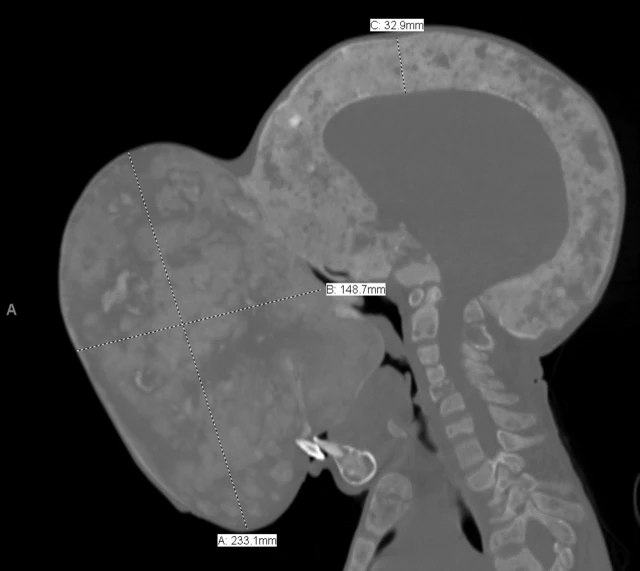

Un tumor del tamaño de una pelota de rubgy le cubre la cara desde hace más dos años y le obstruye el campo visual, las vías nasales y la boca.

Este adolescente cubano, oriundo de la provincia de Villa Clara, en el centro de la isla, tampoco puede ya caminar, porque el peso del quiste (más de 4,5 kilogramos), le impide mantener en equilibrio la cabeza y los médicos temen que, de seguir creciendo, pueda provocarle una fractura fatal de cuello.

"Es un caso atípico y lleno de riesgos, pero la operación es necesaria. Si el tumor sigue creciendo, puede terminar de obstruirle la boca, que es ahora la única vía de entrada de alimentos y aire para él. También el tumor, por su peso y tamaño, podría provocar una fractura de médula al nivel del cuello", explica.

Emanuel sufre una rara condición genética denominada displasia fibrosa poliostótica, que, según explica el doctor Marx, lleva a que surja una mezcla de tejidos y material óseo donde debe crecer un hueso, lo que facilita las deformaciones de sus extremidades o la formación de tumores, generalmente benignos.

"Le es difícil comer, por lo que se encuentra en un estado de malnutrición, pesa 80 libras (36 kilogramos) y 10 son de tumor. También tiene otras deformidades corporales. Si no hacemos esta operación, este tumor podría terminar con su vida", reitera.

"No tenemos idea de cuántas nuevas cirugías vamos a necesitar, pero serán probablemente muchas, ya que este tumor, dada su enorme expansión, ha destruido la mayor parte de la cara de Emanuel. Todo esto si podemos extender su visa médica y reunir las donaciones para seguir haciéndolo", afirma Marx.

"Los principales riegos estarán en encontrar una vía de aire y controlar la pérdida de sangre. El equipo de anestesistas no puede acceder bien a su garganta por la expansión del tumor y como es tan grande y está en una zona tan delicada, tendremos que ser muy precisos y tener mucha precaución para evitar una hemorragia o no afectar sus ojos u otra parte de su cara", explica.